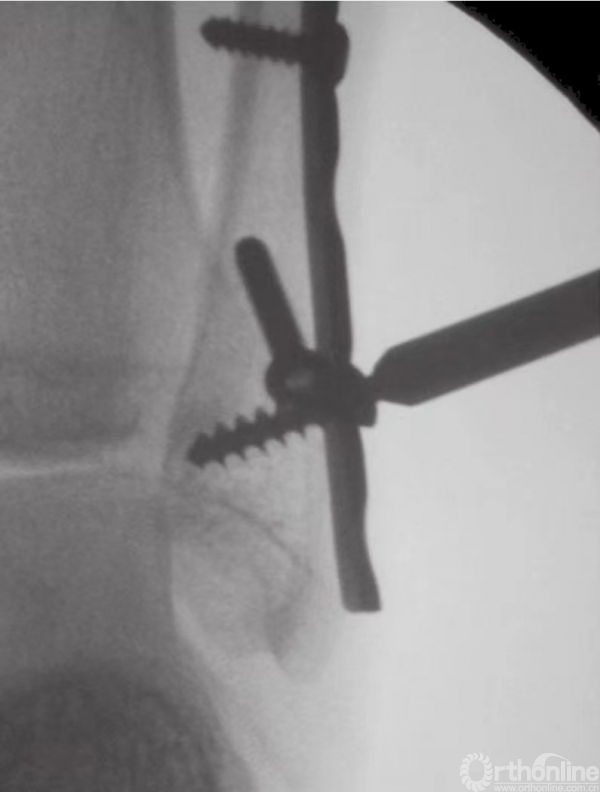

在钳的前方和后方,放置两枚较小的克氏针,并使之与骨折线垂直(图15)。注意要保证克氏针不刺穿踝关节(图16)。为防止刺穿关节,可将角度调至与水平方向约成30°。在克氏针上方和对侧皮质附近,使用管状钻钻孔。后嵌入4mm部分有螺纹的空心松质骨螺钉。

图16 透视下观察克氏针方位及骨折复位情况